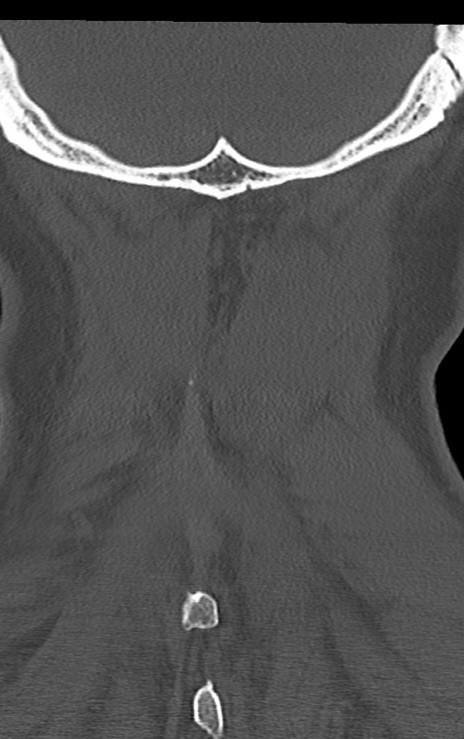

頚椎CT

横断像